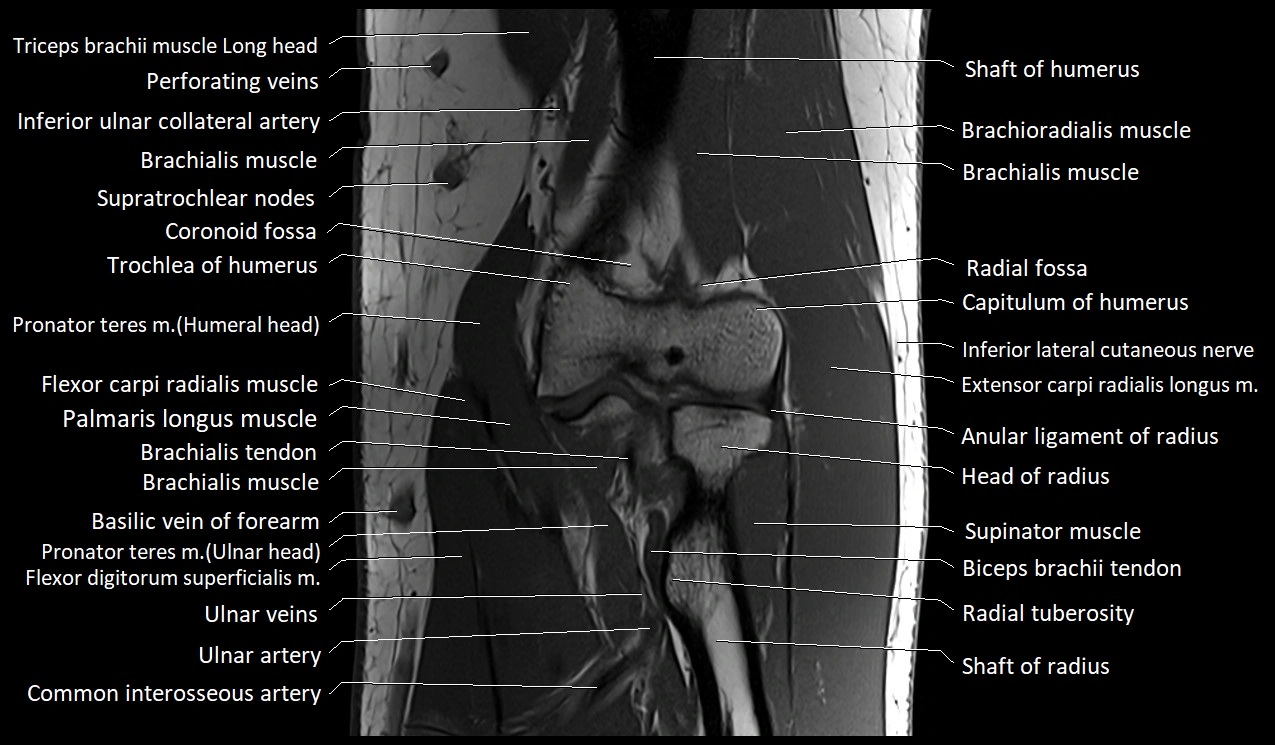

MRI image

image